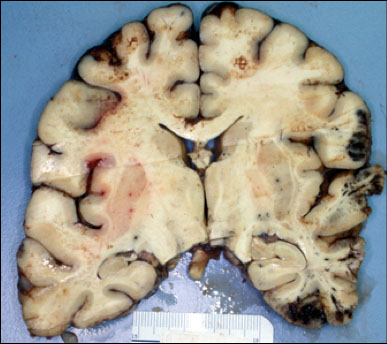

Cerebral contusion in fixed brain

Contrecoup or “gliding” contusions of the medial aspects of the orbital gyri and ventral surfaces of the temporal lobes in man who fell and hit the back of his head.